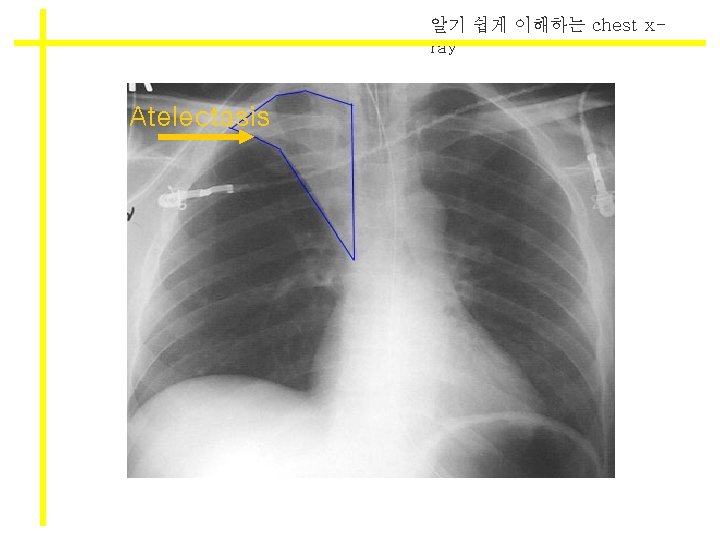

알기 쉽게 이해하는 chest xray Atelectasis

알기 쉽게 이해하는 chest xray Atelectasis VS consolidation l Atelectasis l Density 감소 l Black l Lung volume loss l 무기폐 방향으로 tracheal shifting l Consolidation l Density 감소 l White l 부피는 유지 l 공기가 빠진만큼 뭔 가 replace됨